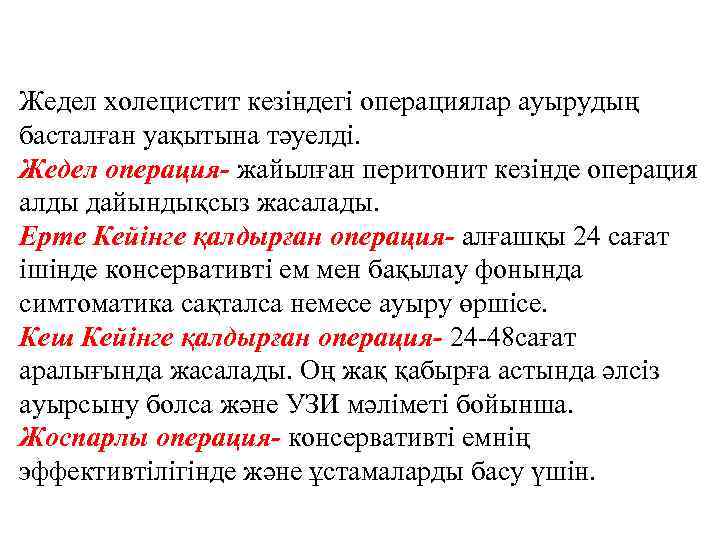

Жедел холецистит кезіндегі операциялар ауырудың басталған уақытына тәуелді. Жедел операция- жайылған перитонит кезінде операция алды дайындықсыз жасалады. Ерте Кейінге қалдырған операция- алғашқы 24 сағат ішінде консервативті ем мен бақылау фонында симтоматика сақталса немесе ауыру өршісе. Кеш Кейінге қалдырған операция- 24 -48 сағат аралығында жасалады. Оң жақ қабырға астында әлсіз ауырсыну болса және УЗИ мәліметі бойынша. Жоспарлы операция- консервативті емнің эффективтілігінде және ұстамаларды басу үшін.